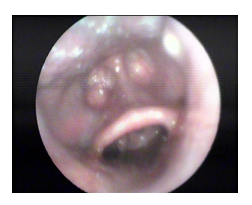

Figure 2 Partial obstruction at the level of soft palate.

Figure 3 Complete latero-lateral collapse at the level of soft palate especially the tonsils.

1. Oropharynx: most patients 75.8% had concentric obstruction while 9.1 % had antero - posterior obstruction and 15.1 % had latero-lateral obstruction.